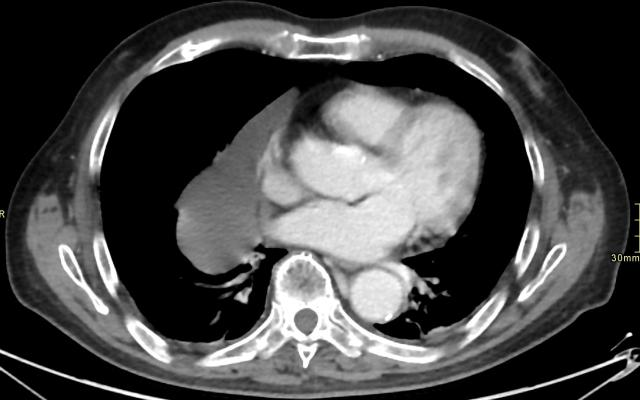

Een 82-jarige man werd door de huisarts verwezen naar onze valpolikliniek vanwege valneiging. De voorgeschiedenis vermeldde een behandelde blaastumor. Behoudens klachten van artrose met ochtendstijfheid kwamen in de anamnese geen bijzonderheden naar voren. Het lichamelijk onderzoek toonde geen afwijkingen. Bij de analyse van de valneiging werd onder meer een röntgenfoto van de longen gemaakt.

Deze röntgenfoto toonde bij toeval een afwijking aan de linker bovenarm, waarna de bovenarm apart werd afgebeeld. We zagen een afwijking met een omvang van 12,0 x 1,5 cm in de proximale humerus, die intramedullair gelegen was in de meta- en diafyse en opgebouwd was…